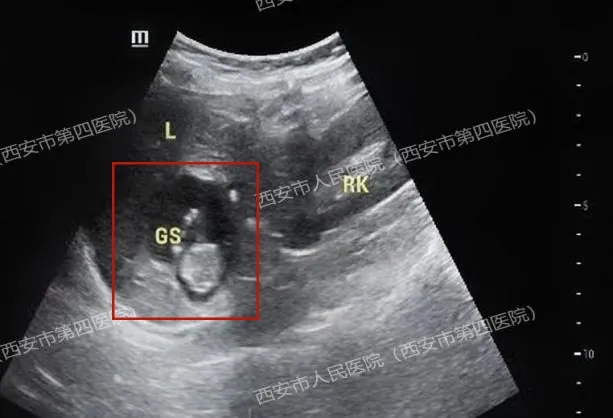

屏幕上,子宫内空空如也,但就在肝脏的边缘,一个清晰的小生命正在有力地搏动!

胎儿,竟然在妈妈的肝脏上“安了家”!这惊心动魄的一幕,近日真实发生在西安市人民医院(西安市第四医院)。

医生觉得疑惑,耐心安抚患者的同时又全面细致的沿子宫周围及上方扩展了扫查范围,当扫查到肝脏时,顿时惊呆了......胎儿竟然长在了肝脏上!!!

胎心搏动强劲有力,胎盘雏形也已形成,测量的顶臀径约36mm,估算的孕周近11周了!

(肝右叶有一个47x35mm的囊实性占位,附件区包块影像显示为卵巢巧克力样囊肿,并非妊娠囊)

受重力影响,受精卵多种植于腹腔内偏低部位,仰卧位时,肝右叶下表面相当于腹腔最低平面,便于附着,且肝包膜、肝实质血供丰富,利于胚胎的生长发育,因此,肝脏异位妊娠多出现在肝脏右叶下表面。